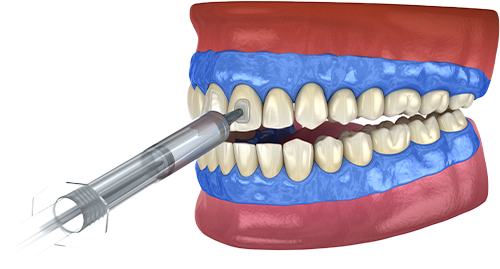

다양한 원인으로 인해 변색되고 착색된 치아의

색을 밝게 만들어 환한 미소와 자신감을 찾아드립니다.

전문가용 치아미백제는 고농도이므로

잇몸에 닿을 시 손상을 야기할 수 있습니다.

연세그리다치과에서는 시술 전 잇몸 보호제를

꼼꼼하게 발라 잇몸 손상을 예방합니다.

검증된 치아 미백제 사용

잇몸 보호제 꼼꼼한 도포

높은 효과

자외선이 아닌 가시광선을 출력하는

LED를 광원을 이용해 타 미백장비에 비해

30% 이상의 효과를 높여줍니다.

정품 미백기 사용

개개인에 알맞게 특수 램프의

강도를 조절할 수 있어 개인별

맞춤치료가 가능합니다.

안정적인 제품

식품의약품 안전처에서

허가받은 미백제만

사용합니다.